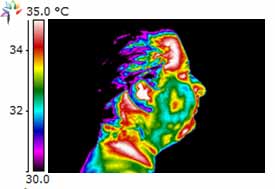

Dental Case Study 1

June 2010 Initial thermography performed.

(L)TMLAT = 0.5 ºC and Hyperthermia in the region of 1st – 2nd premolar.

Dental Exam – no abnormalities, Bite Splint was done. Patient refused any additional dental work.

February 2011 patient complained of sensitivity on chewing in the lower right side.

Exam showed gingival inflammation and furcation involvement of 7mm pocket. Extraction was performed.